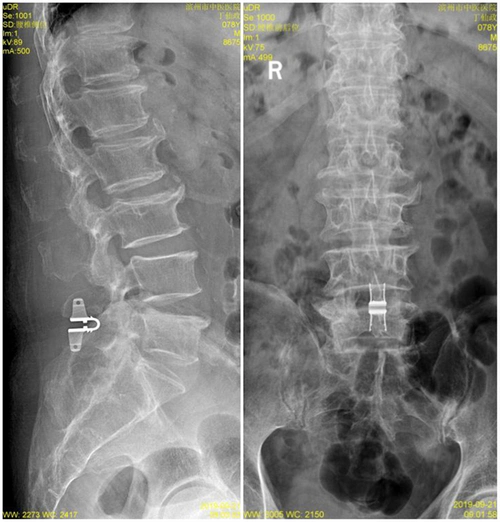

滨州市中医医院成功完成首例腰椎棘突间动态固定手术